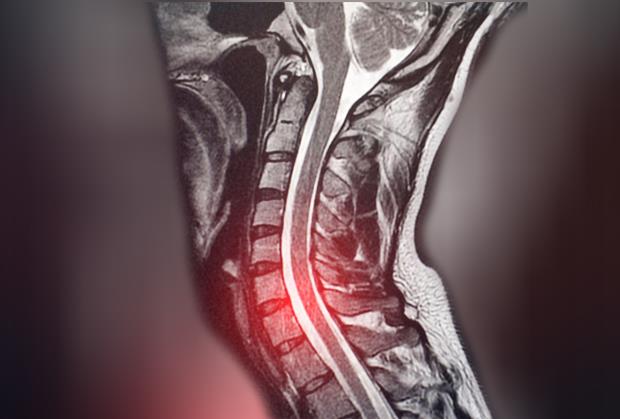

Čovek iz Brazila je prošle nedelje posetio bolnicu u Sao Paolu zbog bola u donjem delu kičme. Verovao je da je problem u diskus herniji i želeo je da to snimi. Snimak je pokazao da je zaista u pitanju diskus hernija, ali i da čovek ima tri bubrega sa kojima je rođen, a da to nije ni znao. Levi bubreg bio mu je sasvim u redu, a pokazalo se da ima i dva spojena desna bubrega.

Mokraćovodi, odnosno ureteri ovog muškarca, spojeni su na ulazu u bešiku.